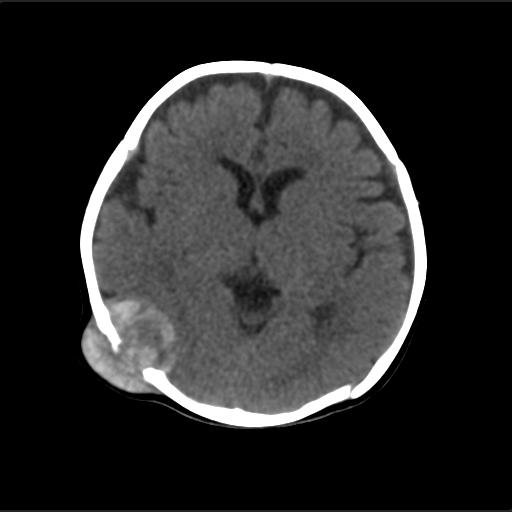

f2m出生已来可见右侧枕部见包块,质地软,无外伤史。包块处ct值16-67hu,大小约3.1x3.2cm左右。

局部颅骨破坏,并以破坏为中心的高密度肿块影,内示软骨影,考虑颅骨软骨瘤.

仔细看颅骨是分离

骨质还算完整。

病灶位于颅缝区,向内外生长,边缘光整。考虑脑膜瘤

血肿机化可能性 比较大,伴双侧额颞顶部硬膜下积液。估计产伤引起